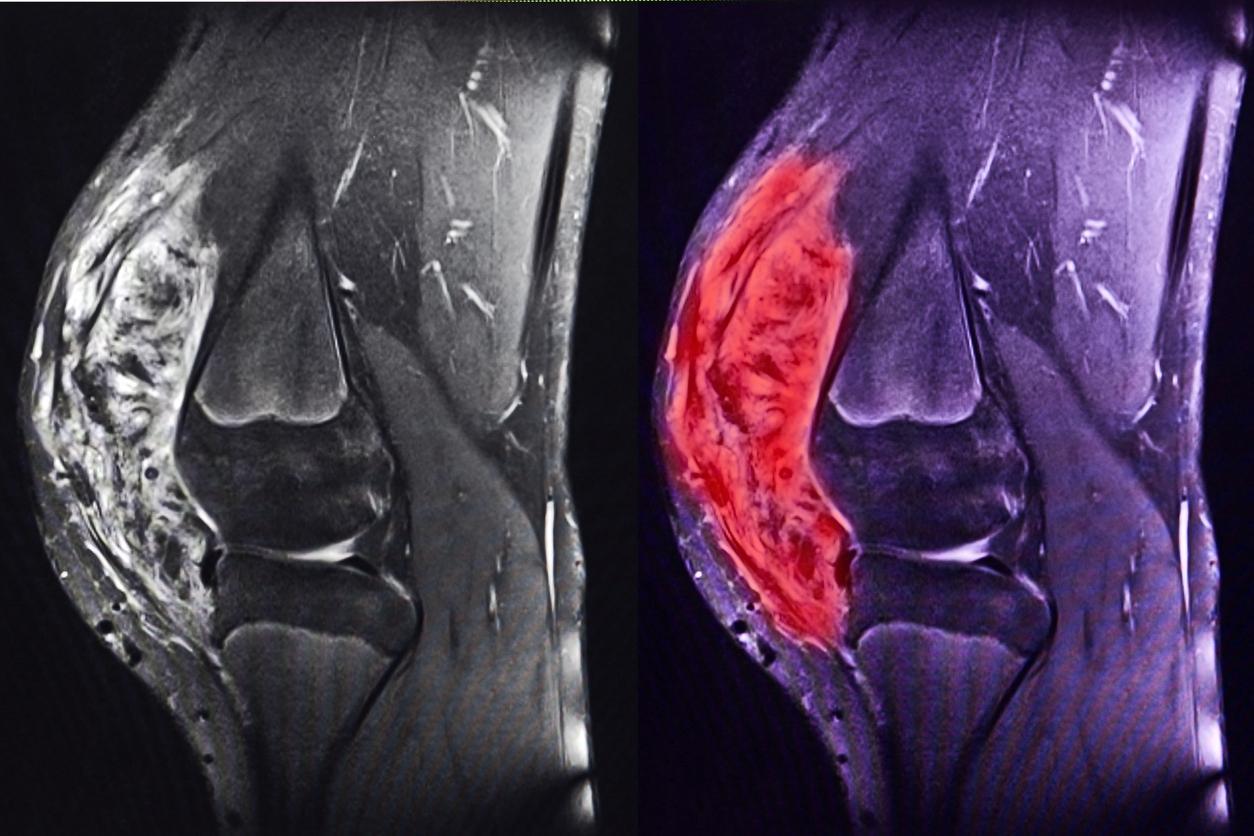

Il existe de très nombreux types de sarcomes. Ils peuvent être classés en trois grandes catégories : les sarcomes des tissus mous, les sarcomes des viscères et les sarcomes des os. Les sarcomes des tissus mous prennent leur origine dans les muscles (léiomyosarcome, rhabdomyosarcome), la graisse (liposarcome), les vaisseaux (angiosarcome), les nerfs etc... ; les sarcomes des viscères peuvent apparaître dans l’utérus ou le tube digestif (GIST) ; les sarcomes osseux se développent à partir des os (ostéosarcome, sarcome d’Ewing), et également du cartilage (chondrosarcome).